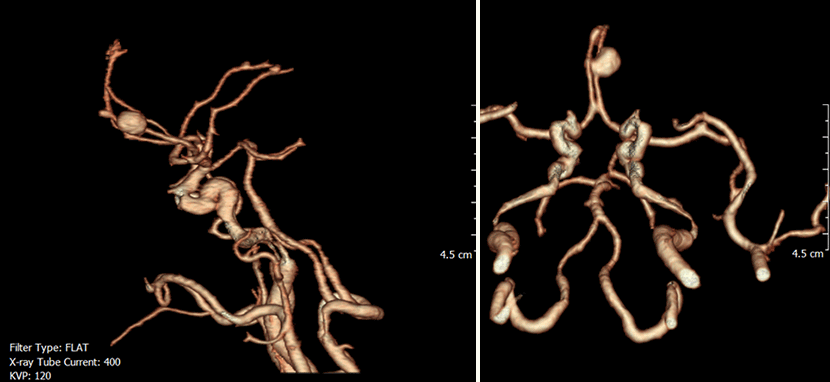

CT 혈관조영술상 뇌동맥류 발견

뇌혈관조영술로 동맥류에 대해 정밀검사

혈관내 코일색전술을 통해 개두술 없이 동맥류를 치료함